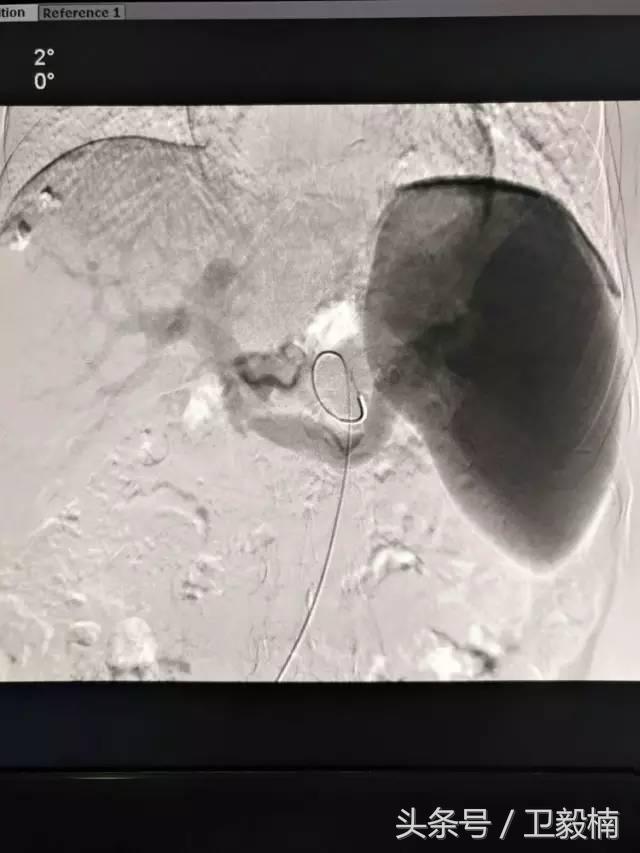

(3)应用栓塞材料,钢圈,内支架治疗动脉瘤、AVM、动静脉瘘,血管性出血。

介入治疗的发展为临床解决了很多难题,使原先不能手术或手术难度很大的疾病得到了简单有效的治疗。比如颈动脉海绵窦瘘,介入应用之前需开颅手术,创伤很大,手术难度大,而介入治疗非常简单的就可以给与治疗,采用球囊栓塞术创伤很小,效果立竿见影。再比如胆管癌,临床上往往引起梗阻性黄疸,外科手术往往切除范围很大,或因为侵犯范围广而不能手术,而介入治疗采用很简单的经皮经肝穿刺术,放入引流管或胆管支架,在此基础上再给与进一步治疗,如植入125I放射性粒子,就可以给与有效地治疗。肝癌患者到了晚期,往往因为患者身体状况差不能接受外科手术,其他治疗效果不好,而采用介入治疗就可以收到很好的效果,减轻临场症状,延长生存时间,我们治疗过很多不能手术切除的肝癌病人,可以生存很长时间。